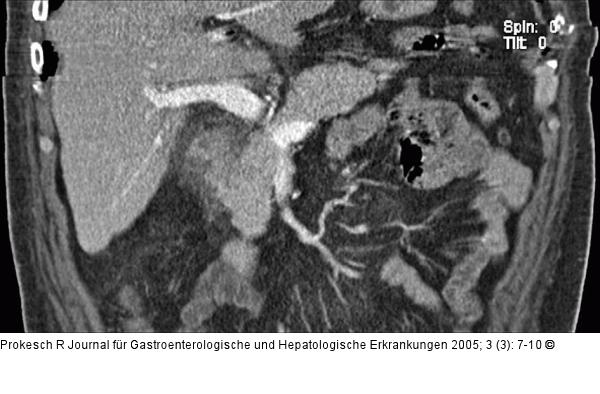

Abbildung 3a-b: Groove-Pankreatitis Pankreatitis, Computertomographie: Mäßiges Ödem zwischen Pankreaskopf und Duodenum (a) sowie im mesenteriellen Fettgewebe (b): Sogenannte Groove-Pankreatitis. |

Pankreatitis, Computertomographie: Mäßiges Ödem zwischen Pankreaskopf und Duodenum (a) sowie im mesenteriellen Fettgewebe (b): Sogenannte Groove-Pankreatitis. |